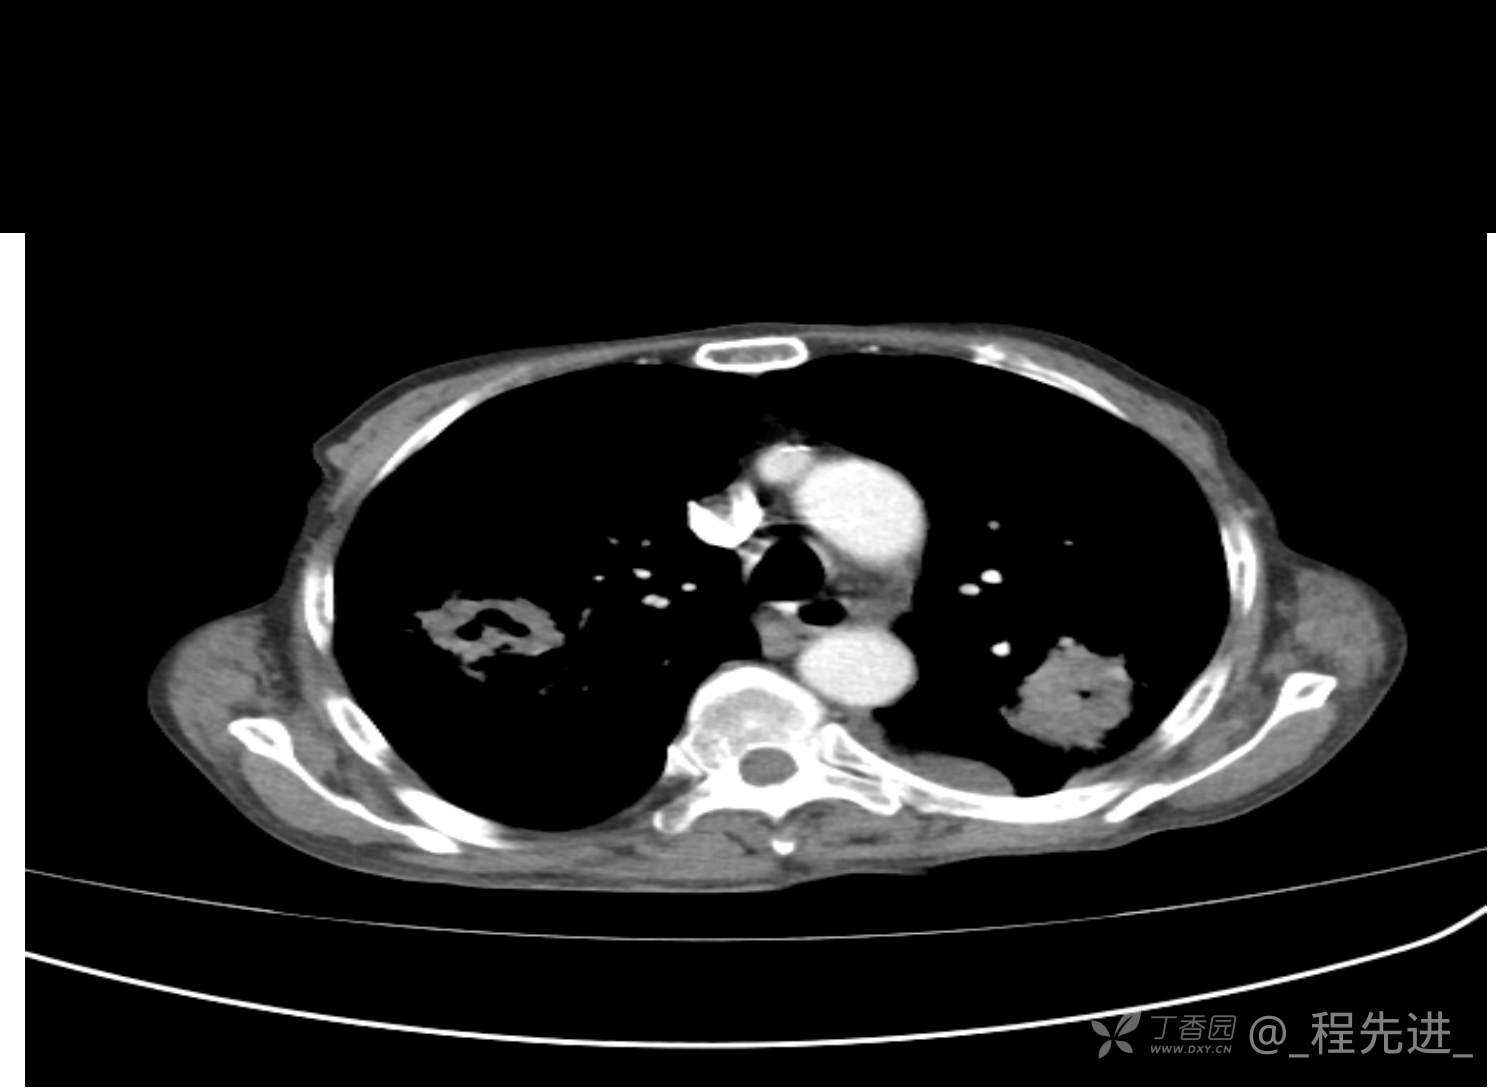

患者性别:男

患者年龄:81岁

简要病史:反复咳嗽、咳痰20余年,加重1周。两肺呼吸音低,可闻及散在干湿啰音。